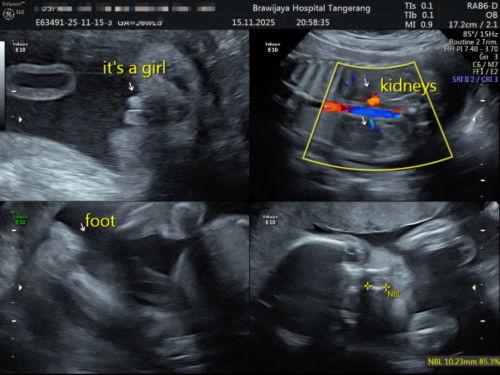

Cewe 100% kah?

Bun mau tanya ini usg 23minggu kek gini 100persen cewe kah? Kata dokter nya sii 100persen#bantujawab #firstmom #sharing